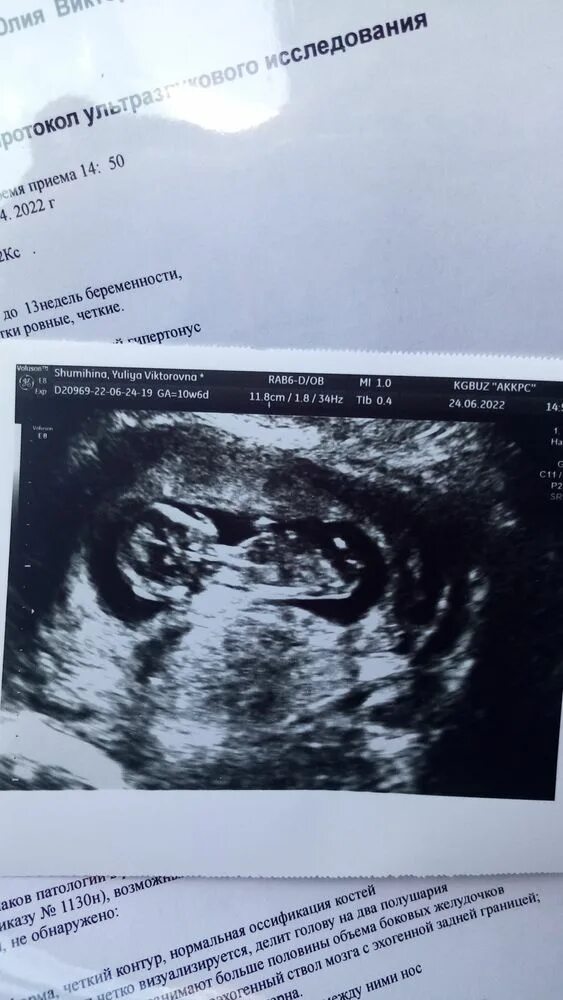

Сколько по времени длится скрининг 1